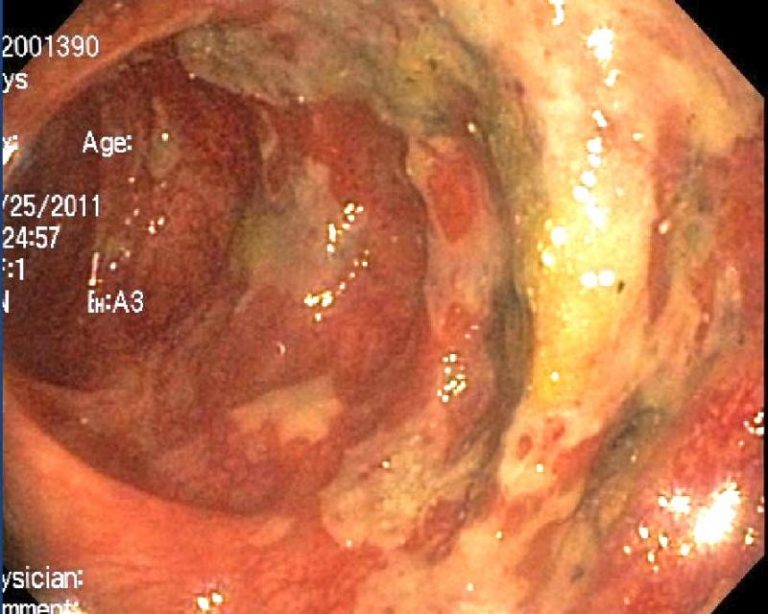

Mucoid plaque removed from the colon.

“That 40 pounds was due to caked layers of encrusted mucus, mixed with fecal matter, resembling hardened blackish-green truck tire rubber or an old piece of dried rawhide.”

Most would be utterly appalled to see the images of mucoid plaque taken from the colon. It acts as a mirror into our past, from infancy to adulthood, of all the choices around food we were faced with or made which led to the symptoms of disease we experience today. (Check out 7:08 in the video below to see the colon of a breast cancer patient.)